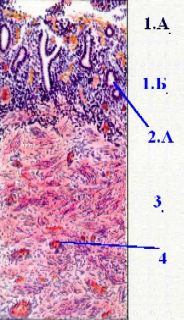

| Слои миометрия | В миометрии – 3 гладкомышечных слоя: подслизистый (5А) – внутренний; не следует путать этот слой с подслизистой основой, которой в матке нет; | |

сосудистый (5Б) – средний; здесь содержатся крупные сосуды и спиралевидно закручиваются артерии, питающие функциональный слой эндометрия; надсосудистый (5В) – наружный. | ||

| Периметрий и окружение матки | а) В основе периметрия – рыхлая волокнистая соединительная ткань с большим количеством сосудов и жировых клеток. б) Вокруг шейки матки имеется скопление жировой ткани – параметрий. в) С поверхности большая часть матки покрыта мезотелием. | |

| Сосуды матки | 1. Под периметрием и в толще мио- и эндометрия идут многочисленные сосуды (4). 2. а) Значительное их число, как уже было сказано, отличается извилистым, спиралеобразным ходом. б) Для спиралевидных сосудов миометрия (питающих функциональный слой эндометрия) это справедливо всегда, в т.ч. при беременности: | |

так, в последнем случае извилистость хода сосудов облегчает закрытие их просвета после родов. 3. а) Вдоль боковых краёв матки идёт магистральная маточная артерия. б) После родов она тоже становится извилистой – в связи с приспособлением сосуда к уменьшающимся размерам матки. |